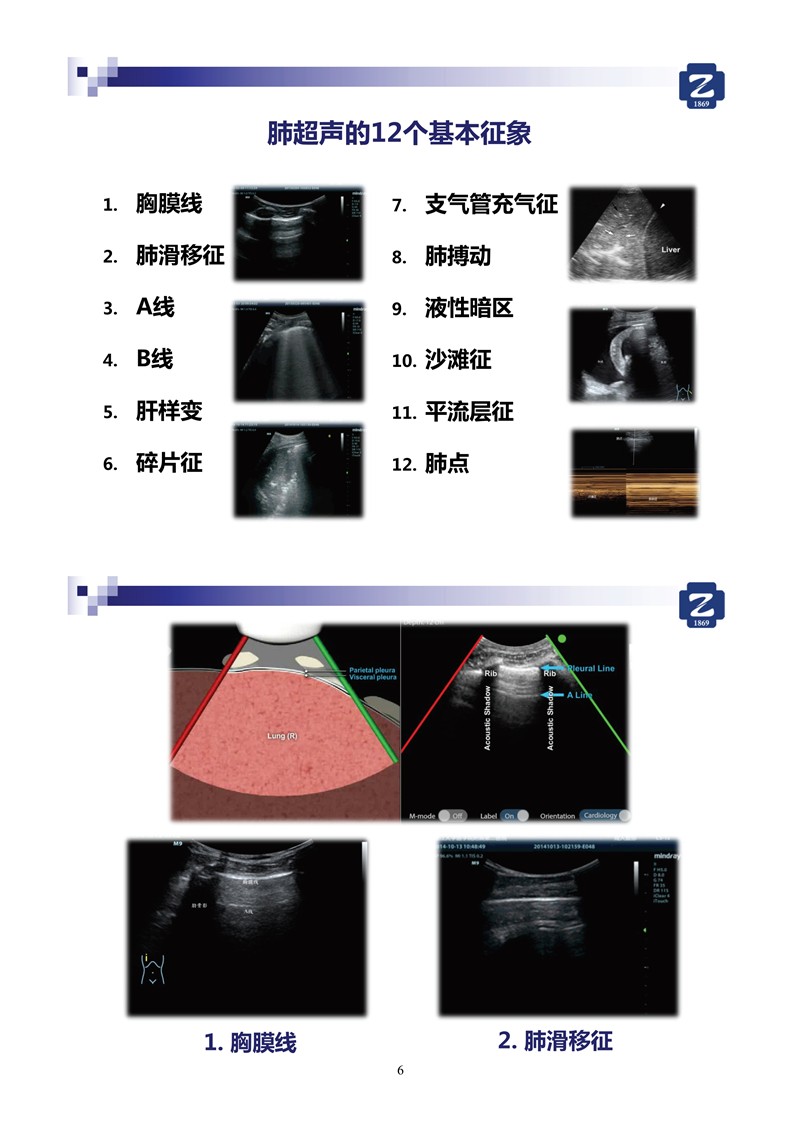

第一版新型冠狀病毒肺炎超聲診斷實(shí)用手冊(全文)

新冠肺超聲實(shí)用手冊(2)_35.jpg